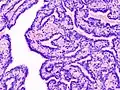

Histopathology of intraductal papilloma of the breast by excisional biopsy. Immunostaining for p63 protein. | |

Histopathology of intraductal papilloma of the breast by excisional biopsy. Hematoxylin and eosin stain.

Histopathology of intraductal papilloma of the breast by excisional biopsy. Immunostaining for alpha-smooth muscle actin.